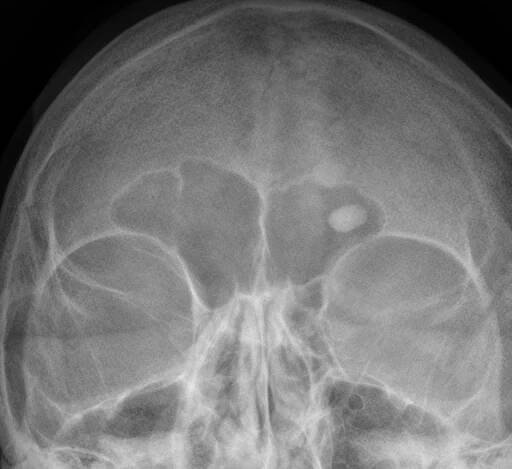

Osteom je benigní nádor kostí. Roste pomalu a vyskytuje se jako lokalizovaný novotvar v kostní substanci. Vzniká hlavně v kostech lebky, zejména v nosní dutině. Wikipedie

Osteomy jsou novotvary, jejichž mateřskou skladební tkání je kost. Z hlediska histologického se rozeznávají osteoma durum (eburneum), převládá-li v mikroskopickém obraze kompakta, osteoma spongiosum, jestliže se na skladbě nádoru podílí…